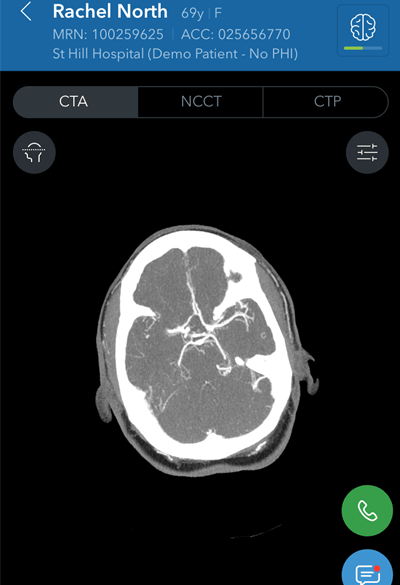

Viz LVO CT artificial intelligence software, Viz.ai

Artificial intelligence (AI) software developer Viz.ai received U.S. Food and Drug Administration (FDA) marketing authorization in February for Viz LVO, an AI-based application that analyzes CT angiography images and notifies providers that their patient may be having a stroke.

After being notified of a suspected large vessel occlusion (LVO) stroke via a text message, neurologists and interventionalists can then view the patient's images, according to the vendor. Notably, Viz LVO was cleared early in 2018 by the FDA's via its "de novo" premarket review pathway, which allows vendors to petition the FDA to down-classify a novel device considered to have low to moderate risk and that had not previously been classified by the agency.